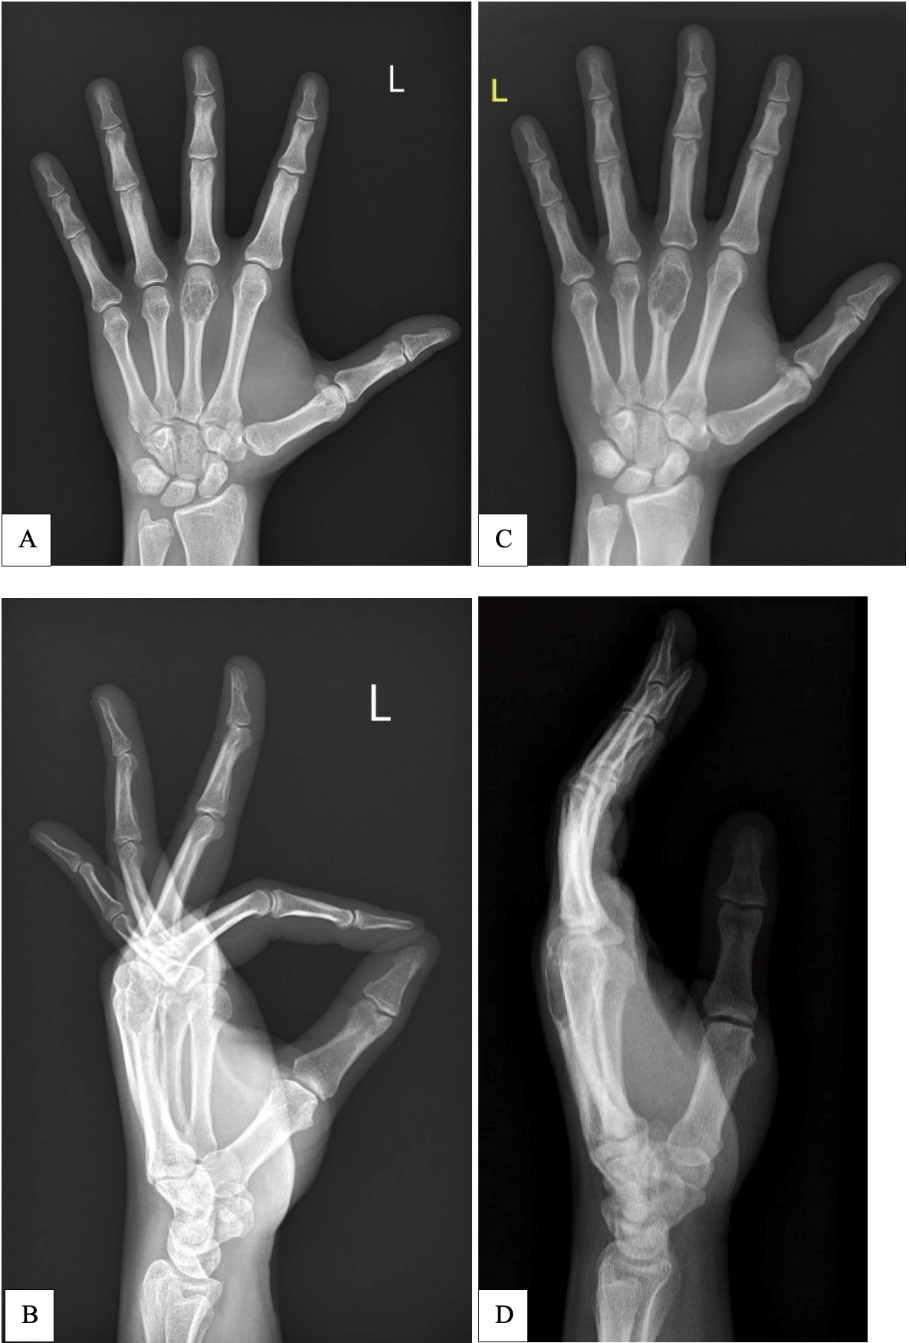

A 35-year-old, otherwise well patient, presented with reduced grip strength in the left hand over a period of a few months. An X-ray revealed a cystic lesion of the third metacarpal suspicious for an enchondroma, with a likely associated, non-displaced pathological fracture that was managed non-operatively. During this period, the patient underwent gentle range of motion exercises and incorporated lifestyle modifications to avoid loading the skeleton. A repeat X-ray six months later showed the cystic third metacarpal lesion with interim growth of roughly 10 mm (Figure 1).

Although both X-rays were reported as an enchondroma by independent consultant radiologists, the interim growth was noted to be unusual. A radiology-guided biopsy was deemed too risky for inducing a fracture; instead the patient had an open curettage and synthetic bone graft under general anaesthesia.